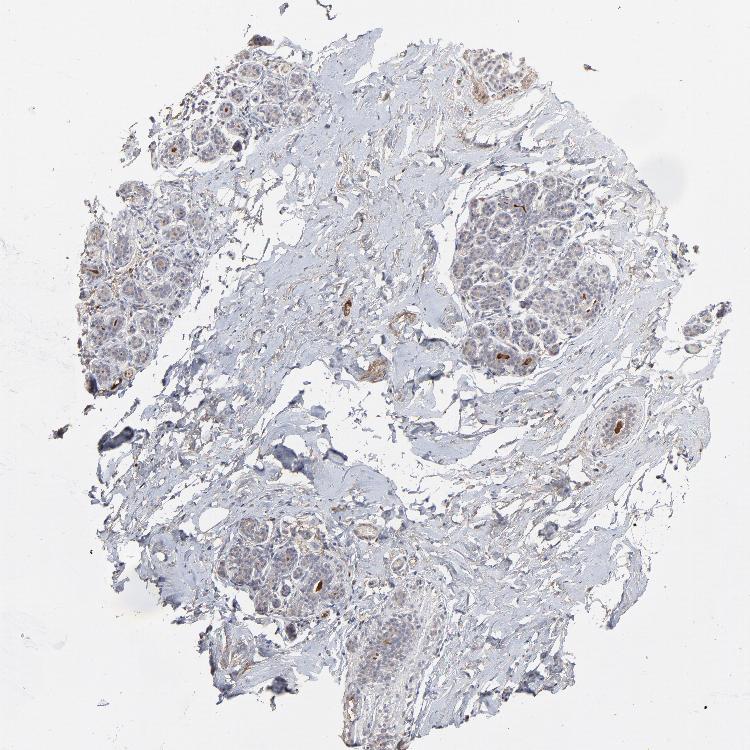

VPREB3